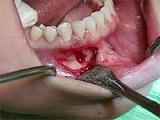

组图为牙瘤的外观及X 线表现,有关此病的描述错误的是 ( )

组图为牙瘤的外观及X 线表现,有关此病的描述错误的是 ( )![]()

A绝大多数为恶性

B生长缓慢,早期无自觉症状

C由牙胚组织异常发育增生而形成

DX 线可见类似发育不全牙的影像

E多见青年人